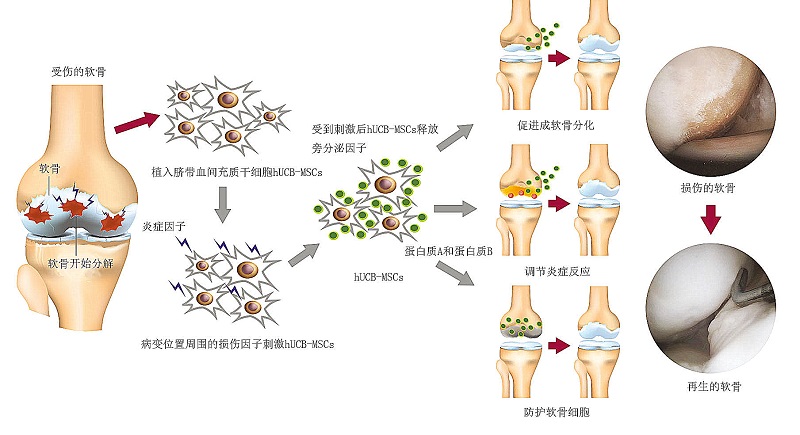

间充质干细胞具有多向分化性、归巢效应以及旁分泌作用,是组织修复中最有潜力的干细胞。CARTISTEM的活性成分为脐血间充质干细胞,间充质干细胞(MSC)具有分化为骨骼、软骨、肌肉、骨髓基质、脂肪的能力。脐血间充质干细胞在损伤软骨微环境中损伤因子的刺激下,还可以分泌生长因子、细胞因子以及配体等复杂基质。

在损伤软骨微环境中损伤因子的作用下,能够刺激同种异体的脐带血间充质干细胞(hUCB-MSCs)分泌蛋白,进而启动复杂的激活机制:促进软骨分化、调节炎症反应、抑制软骨分解蛋白活性、诱导软骨再生。